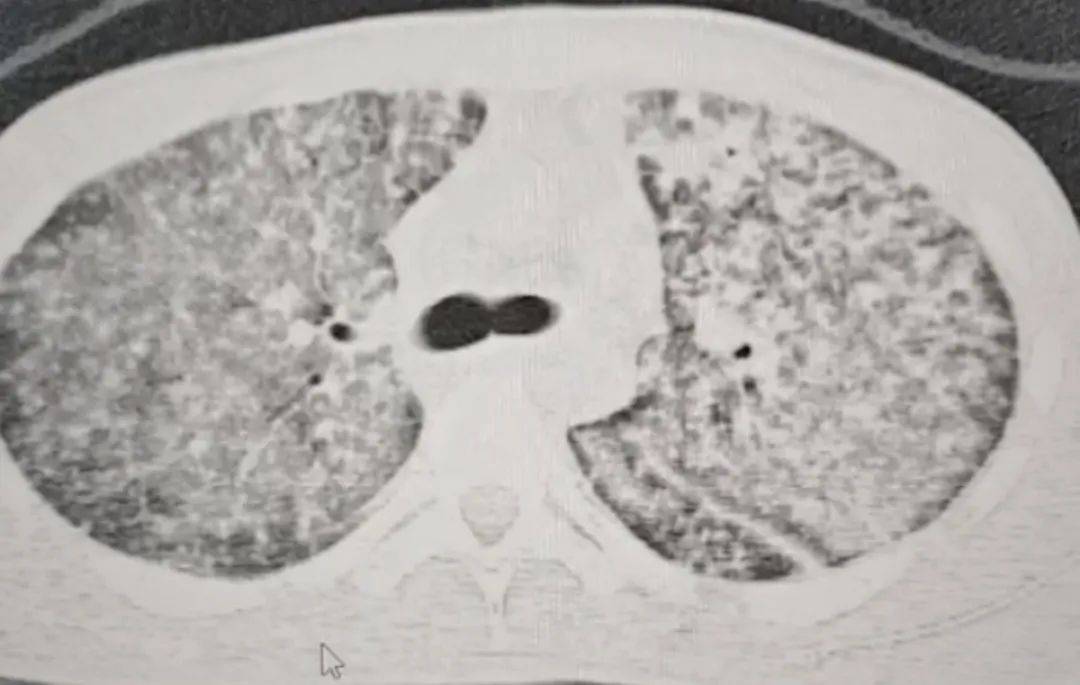

检查结果令医生大为震惊。肺部 CT 影像显示,小王的肺部几乎全白。

同时,指脉氧检测结果也极不理想,正常人的氧合指数在400-500左右,而小王的氧合指数仅有100。

这意味着,小王喘气次数远超常人,可体内氧气含量却远不及常人。医生怀疑小王患上了肺结核,且病情已十分严重,当即建议他转诊至郑州的大医院。

“他来我们医院时,我一看CT,双肺都呈现弥漫性病变,考虑白肺,情况十分危急。” 河南省胸科医院结核内科六/ 感染危重症病区主任梁瑞霞向大河报·豫视频记者讲述,小王因肺部感染引发了急性呼吸窘迫综合征。

三天后,小王的生命体征逐渐趋于稳定。十天后复查肺部CT,病区有明显改变。